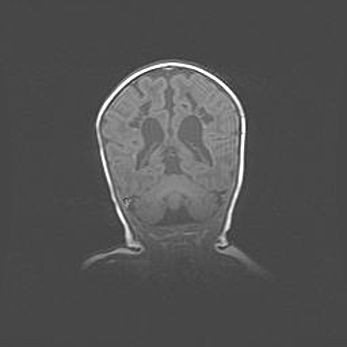

Множественные кисты обоих полушарий головного мозга, наибольшая из них в правой затылочной области. Ассиметричная атрофическая гидроцефалия.

Возраст: 7 месяцев

Вес: 5660 г

Пол: мужской

Окружность головы: 41,5 см

Срок гестации: 28-29 недель

Кисты головного мозга развиваются в результате многоочаговых некрозов вещества мозга и возникают вследствие перенесенной перинатальной инфекции, менингитов, энцефалитов, асфиксии, родовой травмы, расстройств мозгового кровообращения различного генеза. Образованию кист в веществе головного мозга плодов и новорожденных способствуют такие факторы, как высокое содержание в нем воды, недостаточная (или отсутствие) миелинизация и слабая астроглиальная реакция на повреждение.

Кисты могут сочетаться с гидроцефалией и другими поражениями головного мозга.